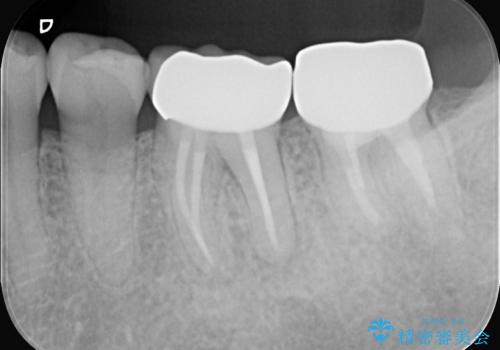

根の病変を精密治療で改善。再発を防ぐ根管治療とオールセラミッククラウン

銀歯からセラミックへ。右上奥歯の精密根管治療と審美修復